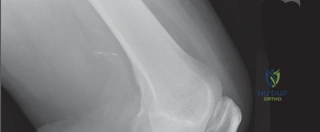

كم سعر وتكلفة عملية مفصل الركبة باليمن؟ دليلك الشامل 2026

تلين غضروف الرضفة: اكتشف الأسباب، الأعراض، وكيفية العلاج الفعال